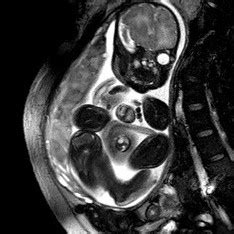

4w5d ultrasound picture!!! | BabyCenter